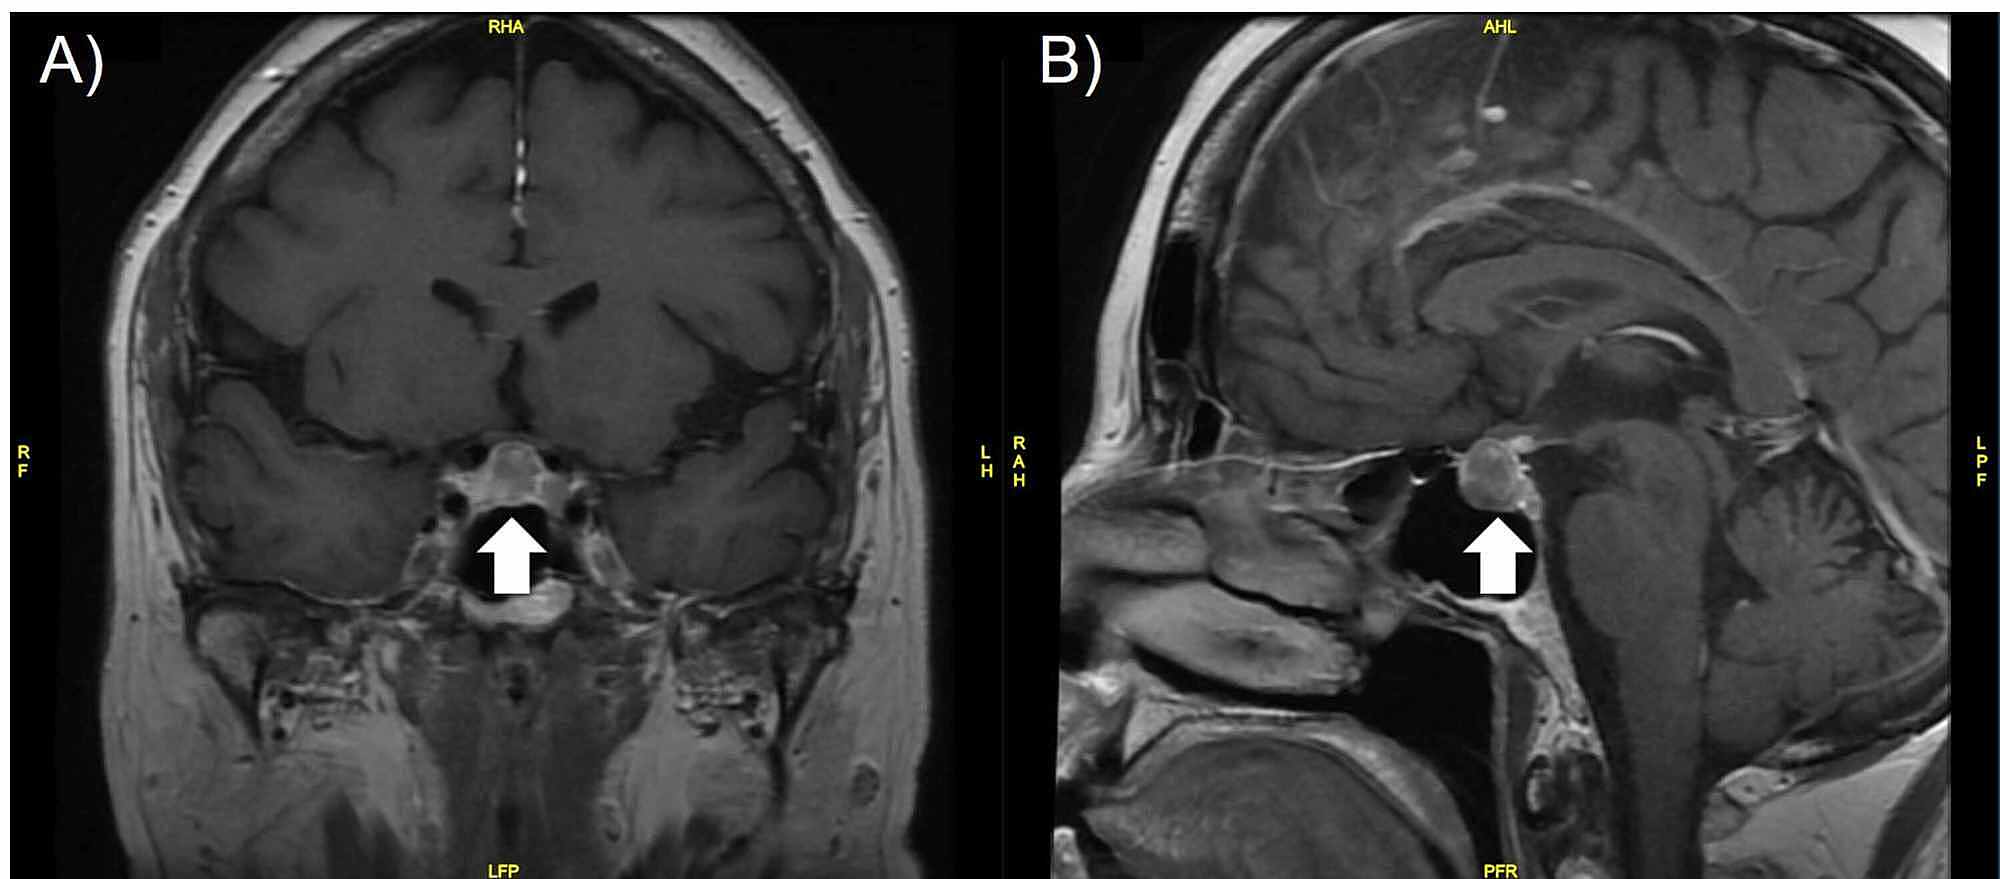

Cureus Pituitary Metastasis Of Pulmonary Large Cell Neuroendocrine Carcinoma A Case Report

www.cureus.com